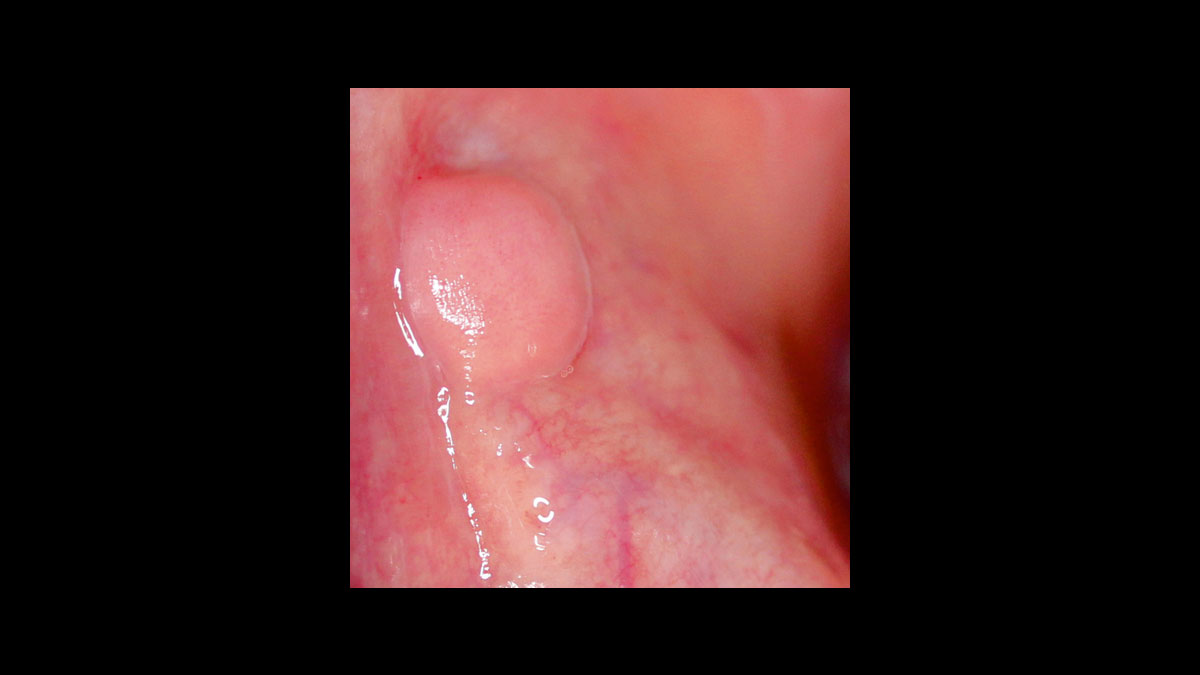

• Abscess